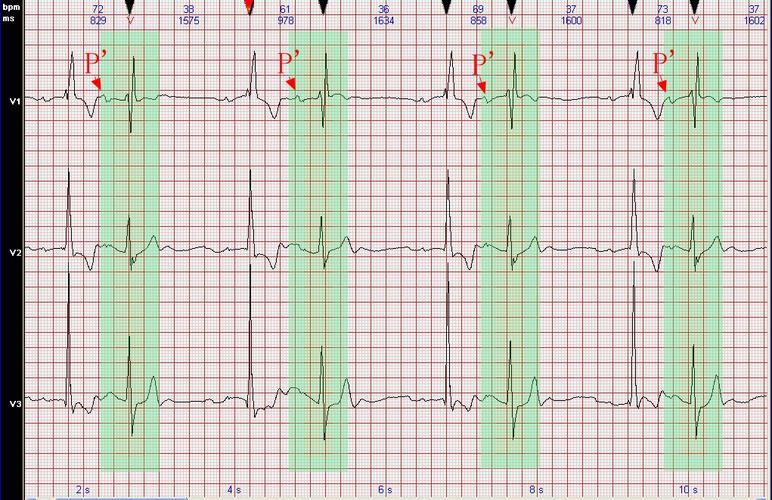

房性早搏二联律心电图

房性早搏二联律心电图,房早二联律心电图表现

窦性心律 2.房性早搏二联律 3.

心电图病例分析:房性早搏伴室内差异性传导呈二联律

【心电图诊断】 ①窦性心律; ②房性早搏二,三联律; ③慢性冠状饿脉

房早二联律心电图表现

房性早搏二联律

房早二联律心电图解析

房早二联律心电图图片

二联律房性早搏